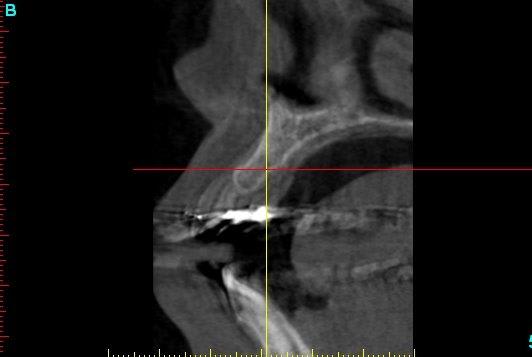

pour ceux que ça intéressent, une petite utilisation d'expansion de la paroi palatine, sur une avulsion d’incisive(racine fendue). toutes mes excuses pour la mauvaise qualité des photos.